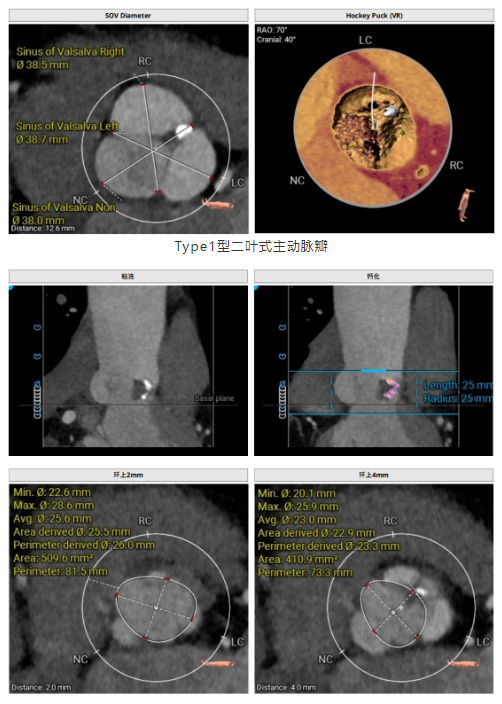

術前超聲和CTA評估提示,患者Type1型二葉主動脈瓣,瓣葉稍增厚,左右冠竇瓣葉交界粘連并鈣化融合,存在三個瓣竇,分布較均勻。主動脈瓣環(huán)直徑26.5mm,左心室流出道直徑27.9mm,STJ直徑31.9mm, 升主動脈擴張,直徑41.7mm;左、右冠脈高度與瓣葉長度適中;左室主動脈夾角為125°,心尖-主動脈夾角偏大。